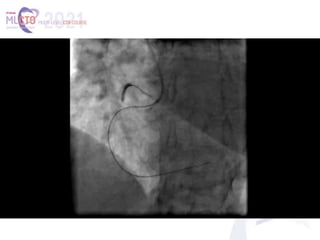

(A, B) The proximal right coronary artery (RCA) occlusion, visualized with separate antegrade and retrograde contrast

injections. Side branch–like, tortuous, continuous transseptal collaterals from the left anterior descending coronary

artery (LAD) supply the distal RCA (white arrow). Notice the mid-LAD severe focal stenosis (yellow arrow). (C) Lesion was

assumingly crossed by antegrade wire escalation, facilitated by proximal anchor technique. Notice the guidewire course

mimicking the imaginary contour of the native RCA artery. Crossing was not confirmed by contralateral injection, and 2

compliant balloons were inflated to dilate the lesion (white arrow). (D) Ellis type III coronary perforation into the

pericardial space (red arrow). (E) Delivery of the microcatheter to the distal cap (white arrow), following proximal

balloon inflation and placement of a pigtail pericardiocentesis catheter. Notice the ectopic guidewire into the

pericardium (red arrows). (F) Wire system externalization through the crossed lesion and the transiently deflated

proximal balloon (white arrow). (G, H) Final result. Sealing by deploying 2 drug-eluting stents, overlapping at the area of

the perforation. The mid-LAD lesion was treated with a drug-eluting stent with a similarly excellent result.